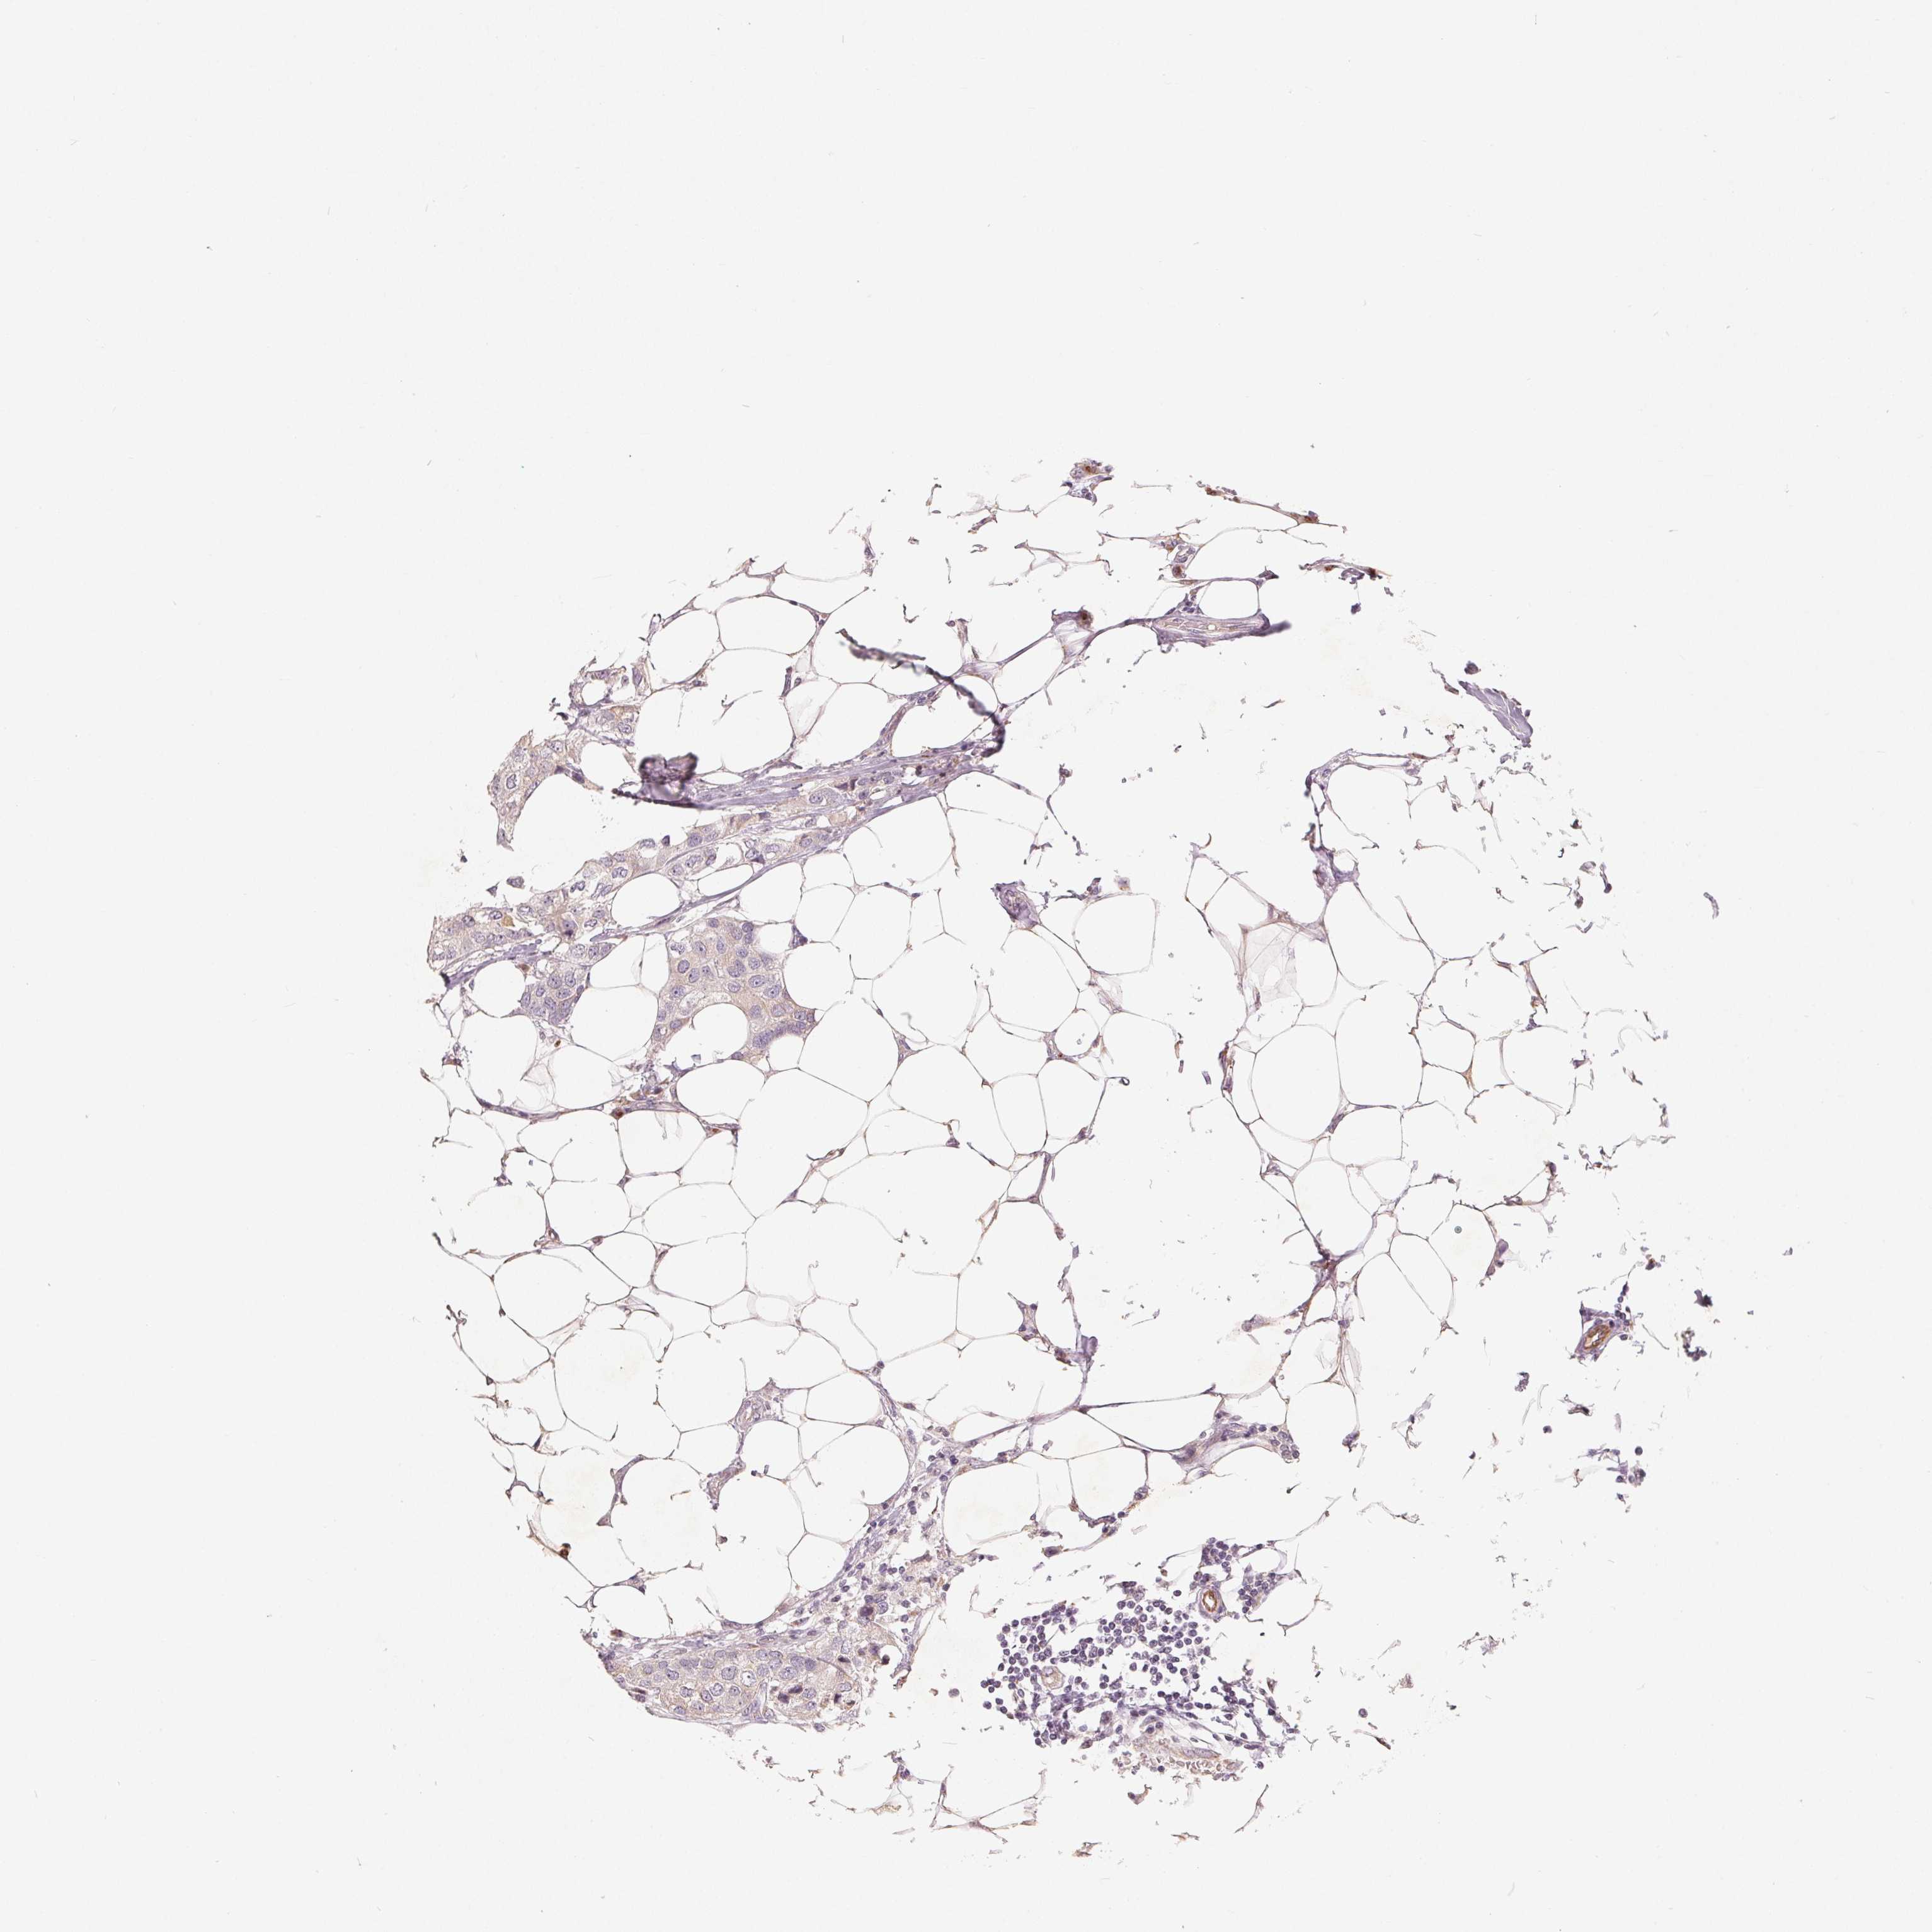

CANCER BREAST CANCER Show tissue menu

BRCA TCGA BRCA VALIDATION PROTEIN EXPRESSION